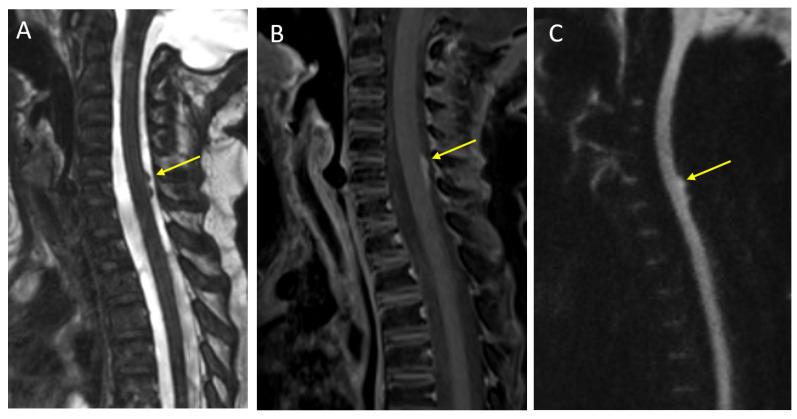

Primary brain tumors are the most common solid neoplasms in children and a leading cause of mortality in this population. MRI plays a central role in the diagnosis, characterization, treatment planning, and disease surveillance of intracranial tumors. The purpose of this review is to provide an overview of imaging methodology, including conventional and advanced MRI techniques, and illustrate the MRI appearances of common pediatric brain tumors.

原发性脑肿瘤是儿童中最常见的实体肿瘤,也是该人群死亡的主要原因。磁共振成像(MRI)在颅内肿瘤的诊断、特征描述、治疗规划和疾病监测中起着核心作用。本综述的目的是概述成像方法,包括传统和先进的MRI技术,并阐述常见儿童脑肿瘤的MRI表现。